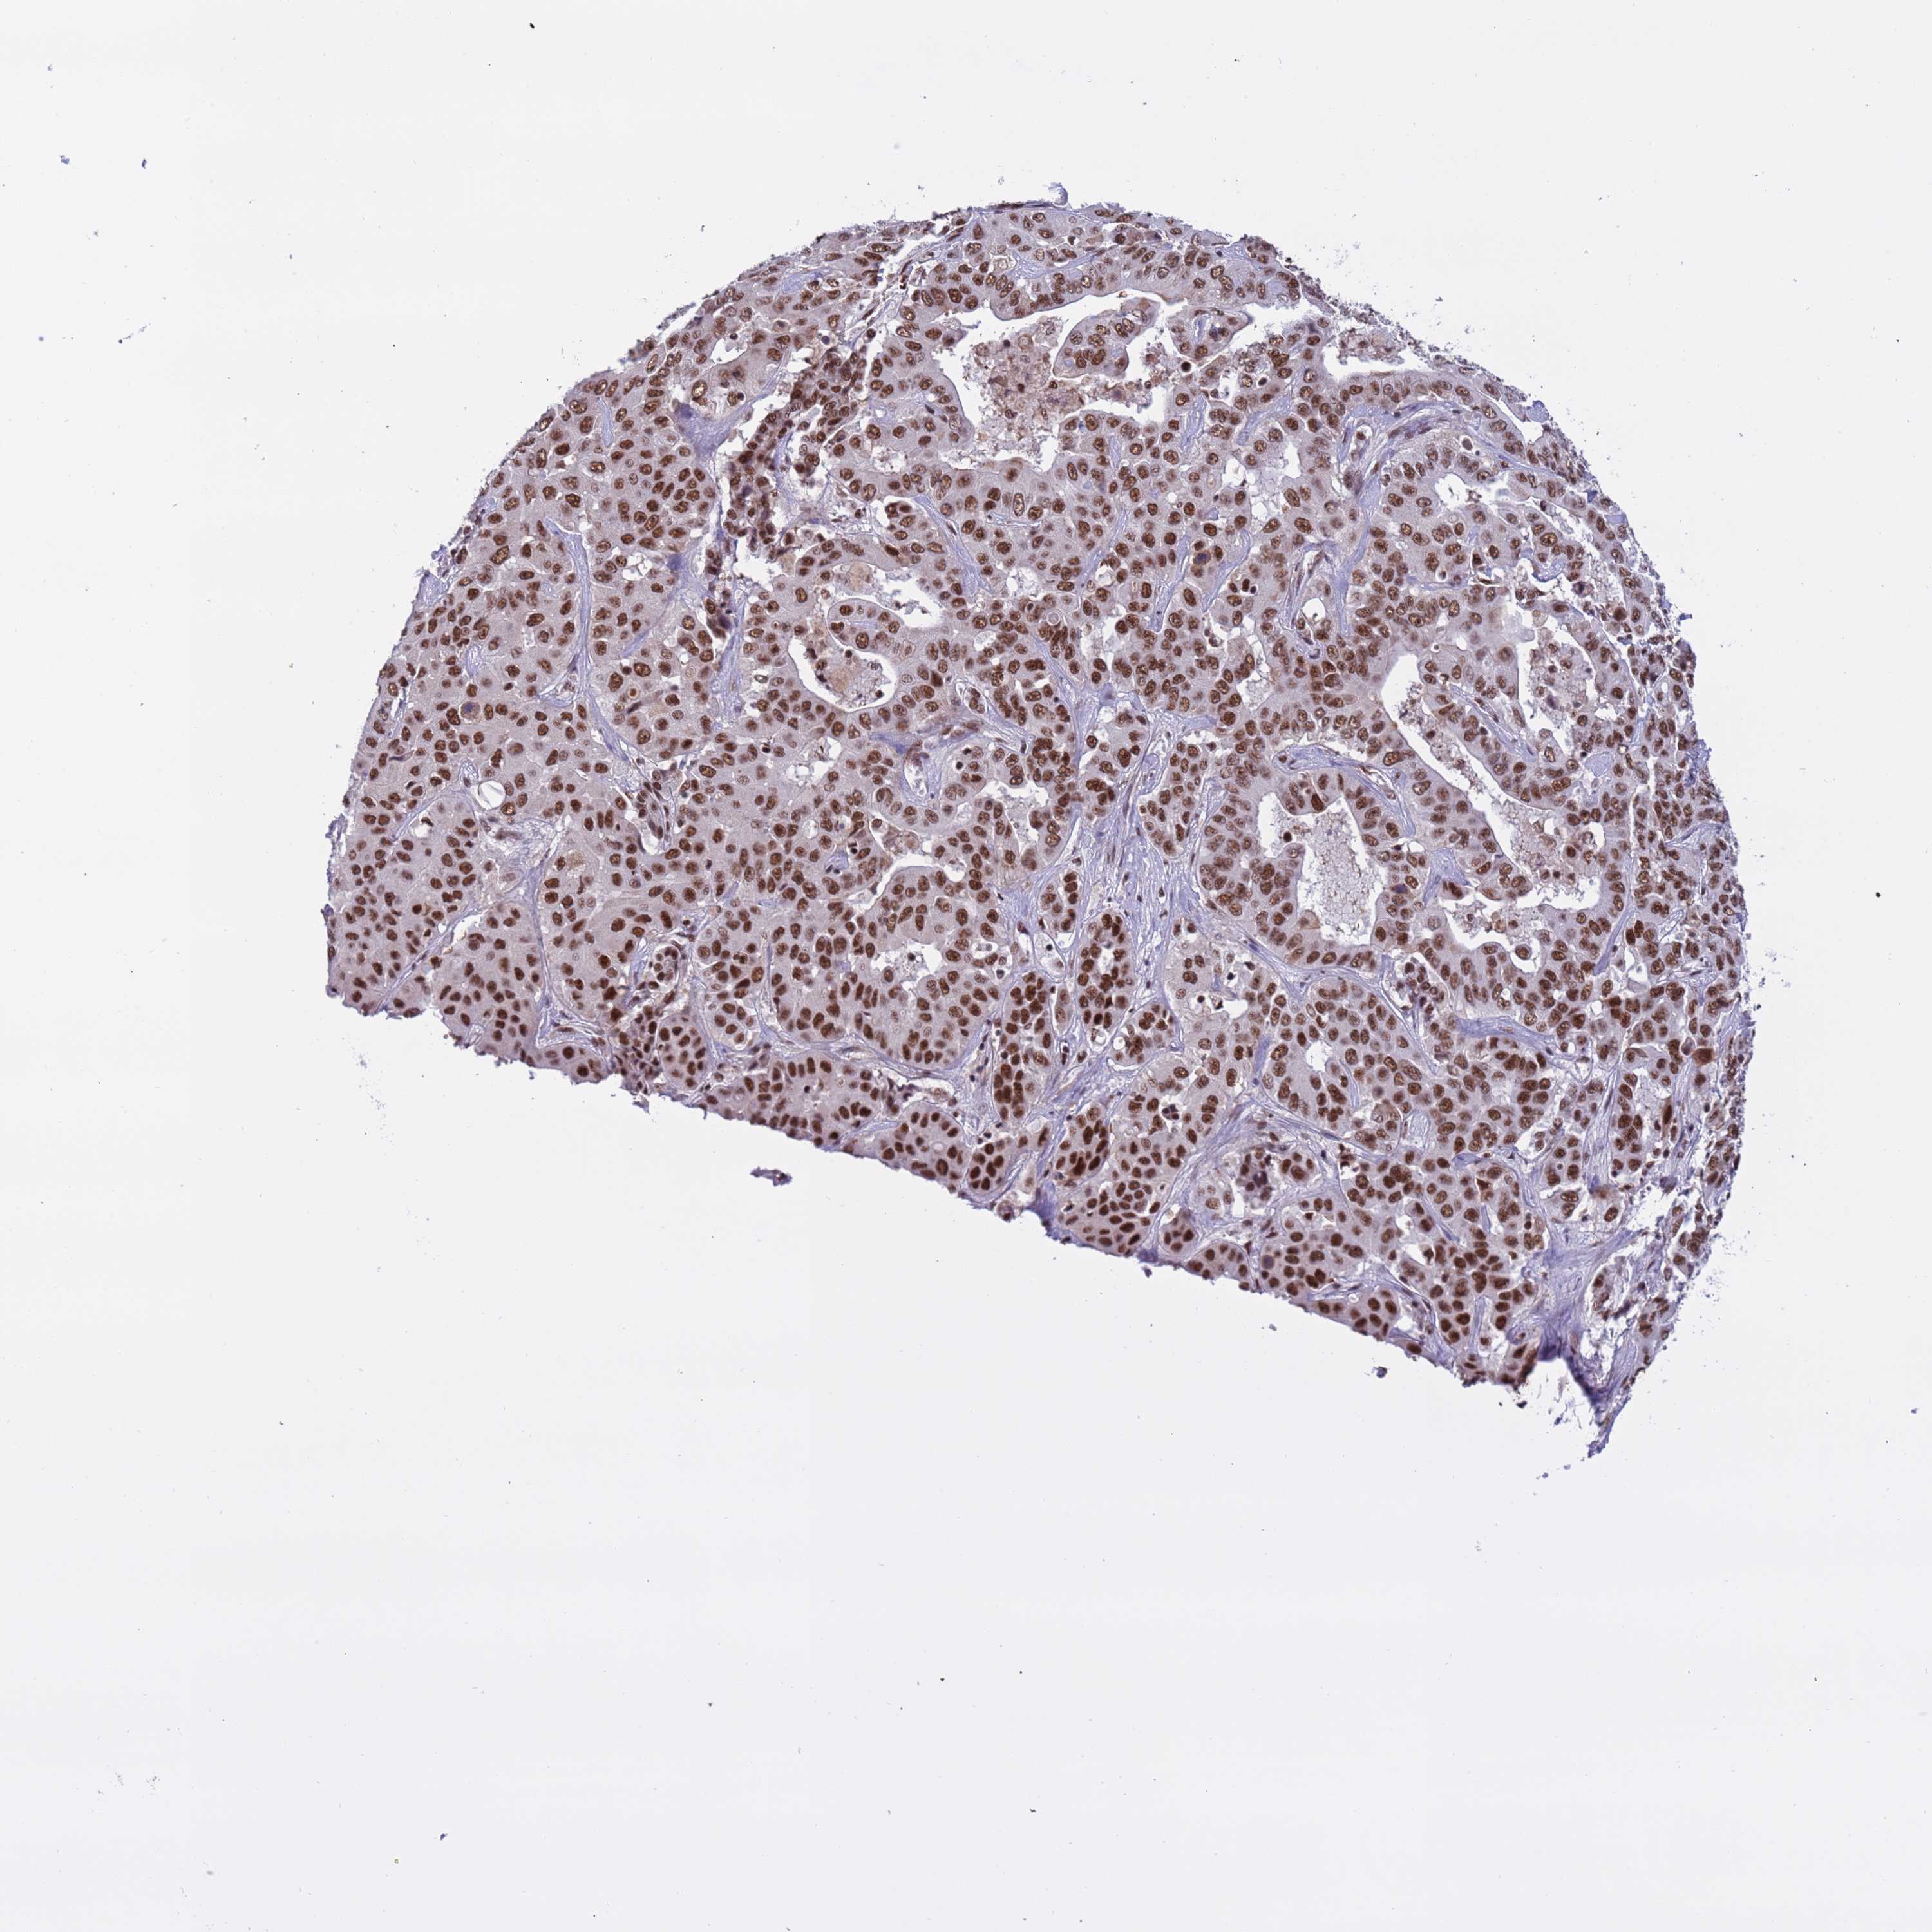

LIVER CANCER - Protein expressioni

A mouse-over function shows sample information and annotation data. Click on an image to view it in a full screen mode. Samples can be filtered based on level of antibody staining by selecting one or several of the following categories: high, medium, low and not detected. The assay and annotation is described here.

Note that samples used for immunohistochemistry by the Human Protein Atlas do not correspond to samples in the TCGA dataset.

Antibody stainingi

Antibody staining in the annotated cell types in the current human tissue is reported as not detected, low, medium, or high, based on conventional immunohistochemistry profiling in selected tissues. This score is based on the combination of the staining intensity and fraction of stained cells.

Each image is clickable and will lead to virtual microscopy that enables deeper exploration of all samples and also displays staining intensity scores, fraction scores and subcellular localization as well as patient and tissue information for each sample.

Antibody HPA042858

Staining

High

Medium

Low

Not detected

Intensity

Strong

Moderate

Weak

Negative

Quantity

>75%

75%-25%

<25%

None

Location

Nuclear

Cytoplasmic/membranous

Cytoplasmic/membranous,nuclear

Cholangiocarcinoma

Carcinoma, Hepatocellular, NOS